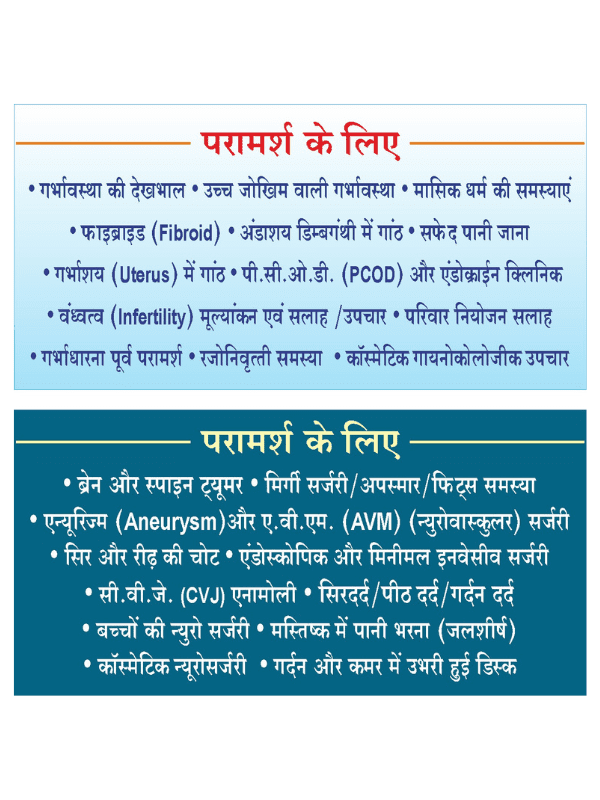

Consultation

We offer expert consultations to promote optimal brain health, providing personalized guidance and care for neurological well-being. Get the expert advice you need to navigate your neurological concerns and optimize your overall health.

Pregnancy Care

Our gynaecologist provides expert pregnancy care, ensuring the health and well-being of both mother and baby throughout the journey.

High Risk Pregnancy

Our skilled gynaecologist specializes in high-risk pregnancy care, providing comprehensive interventions and monitoring to ensure the optimal health and safety of both mother and baby.

Menstrual Problem

Our gynaecologist offers specialized care for menstrual problems, providing targeted interventions and support to alleviate symptoms and promote menstrual health.

Fibroids

Advanced treatment options for fibroids, ensuring symptom relief and preserving fertility when possible.

Ovarian Cyst

Our gynaecologist provides expert care for ovarian cysts, offering comprehensive evaluations and treatments to optimize reproductive health and alleviate symptoms.

PCOS Clinic

Our gynaecologist specializes in PCOS care, offering personalized treatments and support to manage symptoms, improve hormonal balance, and promote overall reproductive health.

Menopause Clinic

Our gynaecologist offers specialized care at our Menopause Clinic, providing comprehensive treatments and support to manage symptoms and promote overall well-being during the menopausal transition.

Vaginal Infection

Our gynaecologist provides expert care for vaginal infections, offering comprehensive evaluations and treatments to restore vaginal health and alleviate symptoms.

Urinary Tract Infection

Our gynaecologist specializes in the treatment of urinary tract infections, providing comprehensive care and interventions to restore urinary health and alleviate symptoms.

Pre-Conceptional Counceling

Our gynaecologist offers pre-conceptional counseling, providing expert guidance and support to optimize health and address any neurological considerations for couples planning to conceive.

Family Planning Advice

Our gynaecologist provides comprehensive family planning advice, offering expert guidance and support to ensure optimal health and address any neurological considerations for individuals and couples making reproductive decisions.

Infertility Evaluation

Our gynaecologist specializes in conducting comprehensive infertility evaluations, offering expert insights and personalized interventions to identify and address potential neurological factors impacting fertility.

Cosmetic Gynaecology

Our gynaecologist offers specialized care in cosmetic gynecology, providing personalized treatments to enhance women's overall health and well-being in a safe and supportive environment.

Cancer Screening

Our gynaecologist provides thorough cancer screening services, utilizing advanced diagnostic techniques to detect early signs of cancer and promote proactive measures for optimal health outcomes.

Brain Tumour

Our neurosurgeon specializes in the diagnosis and treatment of brain tumors, offering comprehensive care and personalized interventions to optimize neurological health and improve outcomes.

Spinal Tumour

Our neurosurgeon provides specialized care for spine tumors, offering comprehensive evaluations and treatments to optimize spinal health and improve overall well-being.

Epilepsy Surgery

Our neurosurgeon performs epilepsy surgeries, providing targeted interventions to manage seizures and improve the overall health and quality of life for individuals with epilepsy.

Aneurysm

Our neurosurgeon offers expert care for aneurysms, providing comprehensive evaluations and treatments to reduce the risk of rupture and promote neurological health.

Neuro Vascular Surgery (AVM)

Our neurosurgeon specializes in neurovascular surgery, offering advanced interventions to treat vascular disorders, optimize blood flow, and improve overall neurological health.

Spinal Injury Management

Our neurosurgeon provides comprehensive care for spinal injuries, offering specialized management strategies to optimize recovery, improve functionality, and enhance overall spinal health.

Head Injury Management

Our neurosurgeon offers expert care for head injuries, providing comprehensive management strategies to optimize recovery, minimize complications, and promote overall neurological health.

Endoscopic Surgery

Our neurosurgeon performs advanced endoscopic surgeries, utilizing minimally invasive techniques to treat neurological conditions and optimize overall health outcomes.

CVJ Anomaly

Our neurosurgeon specializes in the treatment of craniovertebral junction (CVJ) anomalies, providing expert care and interventions to optimize neurological health and ensure proper alignment of the skull and spine.

Headache

Our neurosurgeon offers specialized care for headaches, providing comprehensive evaluations and personalized treatments to alleviate symptoms and improve overall neurological well-being.

Back Ache

Our neurosurgeon specializes in the treatment of backaches, providing comprehensive evaluations and personalized interventions to alleviate pain, improve functionality, and enhance overall spinal health.

Neck Pain

Our neurosurgeon specializes in the treatment of neck pain, providing comprehensive evaluations and personalized interventions to alleviate discomfort, improve mobility, and enhance overall cervical spine health.

Pedriatic Surgery

Our neurosurgeon offers specialized pediatric surgical care, providing comprehensive evaluations and treatments to address neurological conditions and optimize the health and well-being of children.

Hydrocephalus

Our neurosurgeon specializes in the treatment of hydrocephalus, offering comprehensive evaluations and personalized interventions to manage fluid buildup in the brain and promote neurological health.

Cosmetic Neuro Surgery

Our neurosurgeon performs cosmetic neurosurgery, utilizing advanced techniques to address neurological conditions while also improving aesthetic outcomes, promoting both health and appearance.